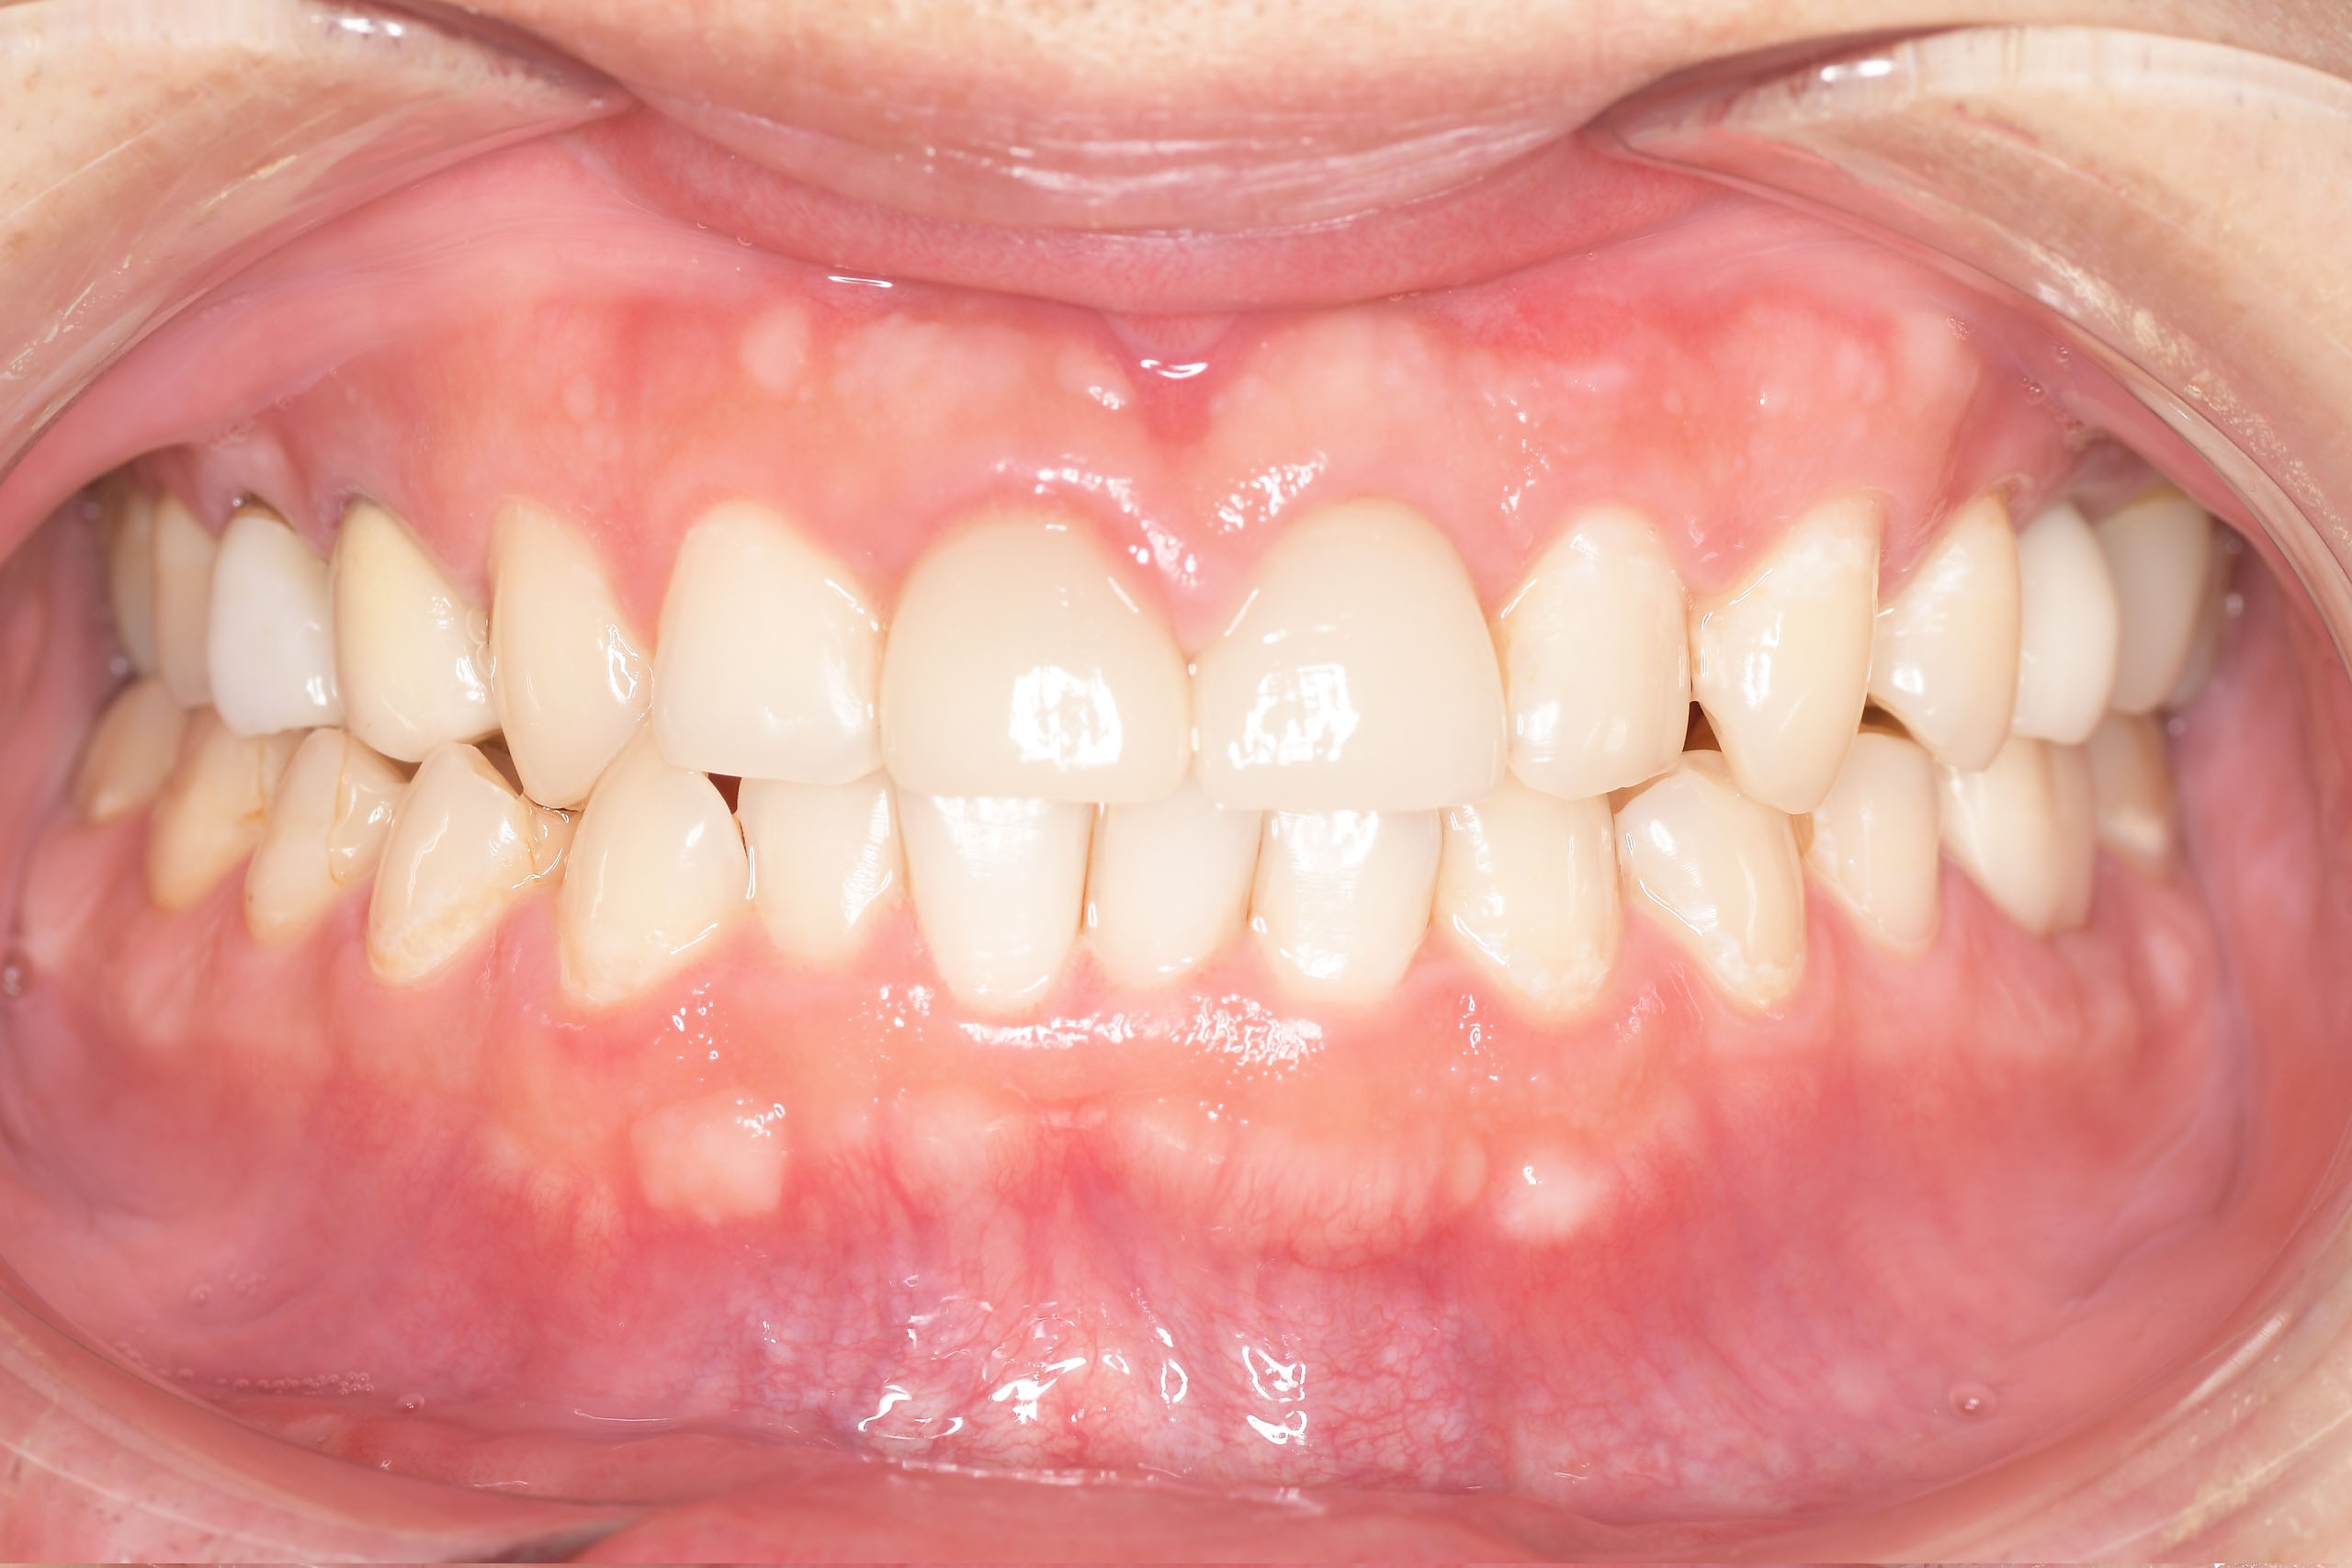

CASE 2

Before

After

基本情報

| 年齢・性別 | 30代・男性 |

| 主訴 | 歯石を取りたい |

| 治療内容 | 超音波スケーラーでの歯石除去 |

| 治療期間 | 60分 |

| 治療費 | 初診料を含め約4,500円 |

| リスク・副作用 | 歯ぐきに違和感や痛みを覚える場合がある。 1週間程度、歯を磨くといつもより出血することがある。 腫れていた歯ぐきが引き締まることで歯ぐきが下がった様に見える。 歯ぐきが下がることで歯がみしやすくなることがある。 一時的に歯の動揺(ゆれ)が増す場合がある。 |